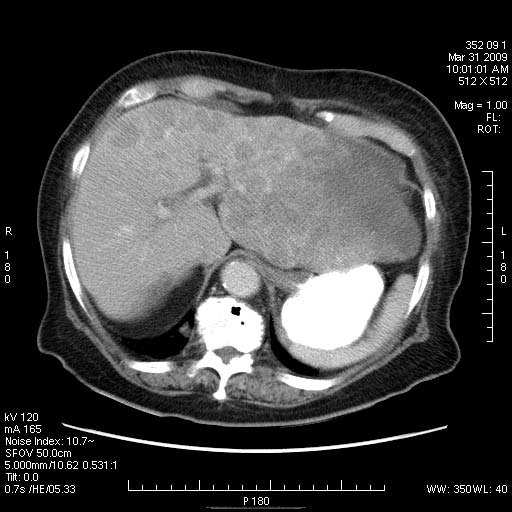

Женщина 82 лет с болями в эпигастральной области.

Такие метастазы в печень очень хорошо видны на поздней артериальной/портальной фазе, с типичным периферическим усилением по типу "кольца".

Заблуждение № 2. «УЗИ является прекрасным методом диагностики метастазов печени». Крайне опасное заблуждение. По современным данным выявляемость метастатических очагов до 3 см при обычном УЗИ может не превышать 45 %, более 3 см – 80 %. Чувствительность УЗИ может быть существенно повышена применением ультразвуковых контрастных средств, однако последние очень дороги и требуют современного ультразвукового оборудования. Вывод: при необходимости выявления очаговых поражений печени необходимо выполнение протоколов КТ. Для уточнения природы выявленных очагов возможно проведение прицельной биопсии под контролем УЗИ.